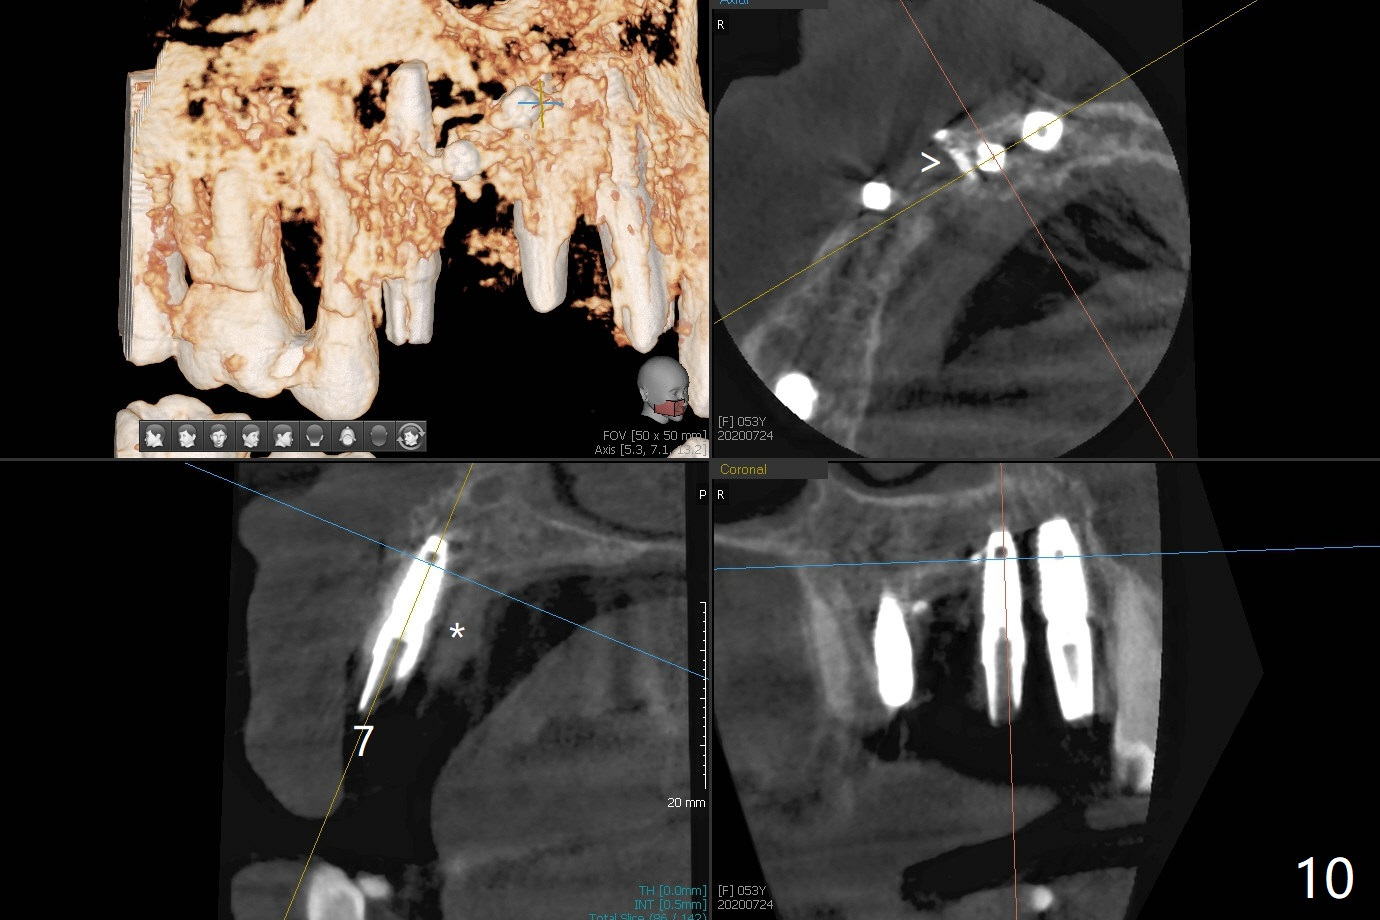

在6,7号牙位牙槽嵴切口,翻瓣,找不到上次放置的tenting screw,不过7号牙位骨质虽然低,够宽的,开始钻洞(图四),植入3.8乘8.5毫米植体,扭力足够(图五),近中舌侧暴露螺纹堆加骨粉(图五*),然后放置基台,再次在后者周围放置骨粉(图五至七),覆盖两张PRF膜后缝合(图八),最后在三个箭头周围放置牙周敷料。术后CT显示植体与tenting screws(图九,十箭头)有一定距离,但是5号牙植体颊侧根尖穿孔(图九 *)。如果植体不脱落,需做侧方切口植骨。术后七天7号植体腭侧肿胀(图十一 *),切开没有脓水,插入牙胶尖,它末端指向7号植体周围tenting screw。后者可能需要拔除,同时5号牙颊侧根尖植骨,但是为时太早,可能打搅骨粉生长。术后两周腭侧肿胀没有消失,但是不痛,继续观察。术后接近6个月,软组织正常(图十三),但是5,7植体周围没有骨质(图十四,五)。由于近中tenting screws周围软组织触痛(局麻不全情况下),螺钉取出(图十六,七(*)),而远中螺钉好像有帮助5植体螺纹骨粉撑起,所以留下(腭侧穿孔部分去除),最后放置粘性骨粉(图十八:*)和PRF膜(两张由7基台打孔固定)。